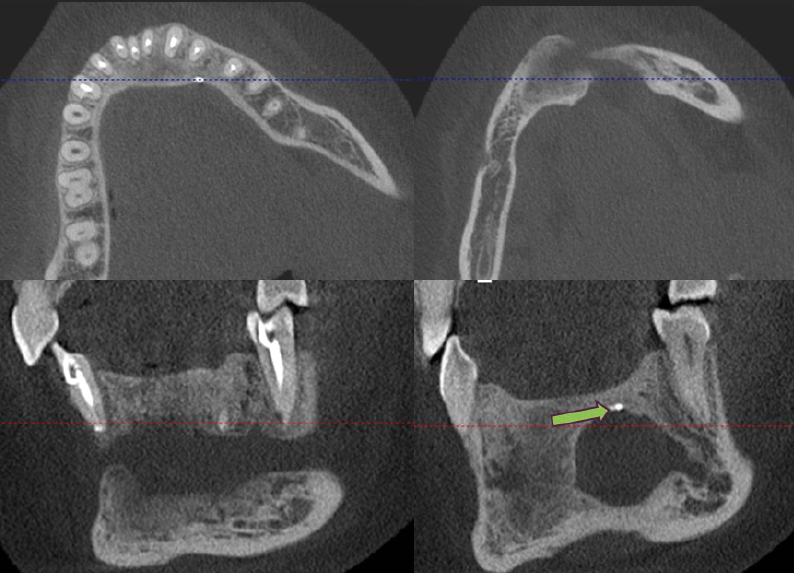

Further three-dimentional imaging was required and a cone beam computed tomography (CBCT) was carried out showing well-defined multilocular hypo-hyperdense lesion, with ill-defined granular wispy septa and granular hyperdense patches. Axial and sagittal cuts revealed expansion and thinning of the labial cortical plate, and perforation of the lingual cortical plate. Double labial cortex of the lesion is obvious reflecting its undulating course. Associated teeth exhibited loss in lamina dura with slight lateral displacement and no root resorption. The lesion also involved the left mental foramen (Figure 3).

Figure 3. Reconstructed panoramic view (A), Axial cut (B), Corrected coronal cut (C), and Sagittal cut (D) respectively showing mixed hypo-hyper dense lesion at the area of the lower anterior teeth. Red arrows show ill-defined granular wispy septa, while green arrows show hyperdense patches of granular appearance.